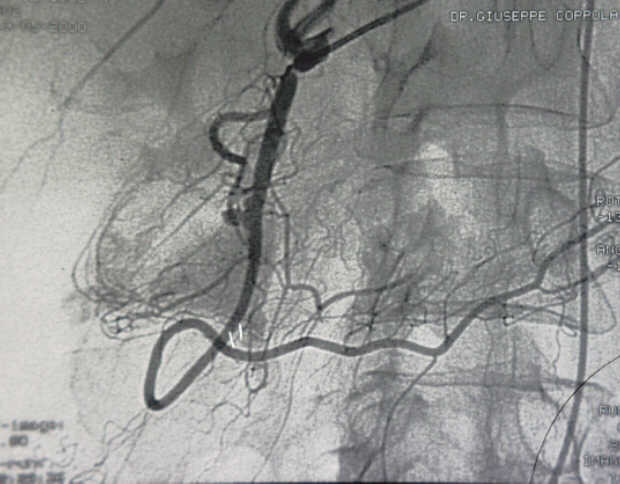

Diagnosis: Angiography

Giuseppe Morelli Coppola, Raffaella Niola, Franco Maglione

Unità Operativa di Radiologia Vascolare ed Interventistica, Azienda Ospedaliera "A. Cardarelli". Napoli, Italy